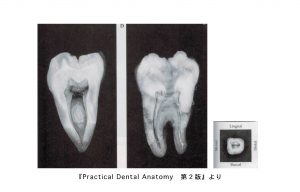

上顎大臼歯の中身

• 歯の外形を縮小した形。

• 髄室角は近心頬側で最も鋭く突出する。

• 根管数は3〜4根管、あるいは2〜1根管認められる。

• 頬側根管は細く彎曲するものから幅広いものまで認められる。

• 近心頬側根管では2根管が50%存在する。